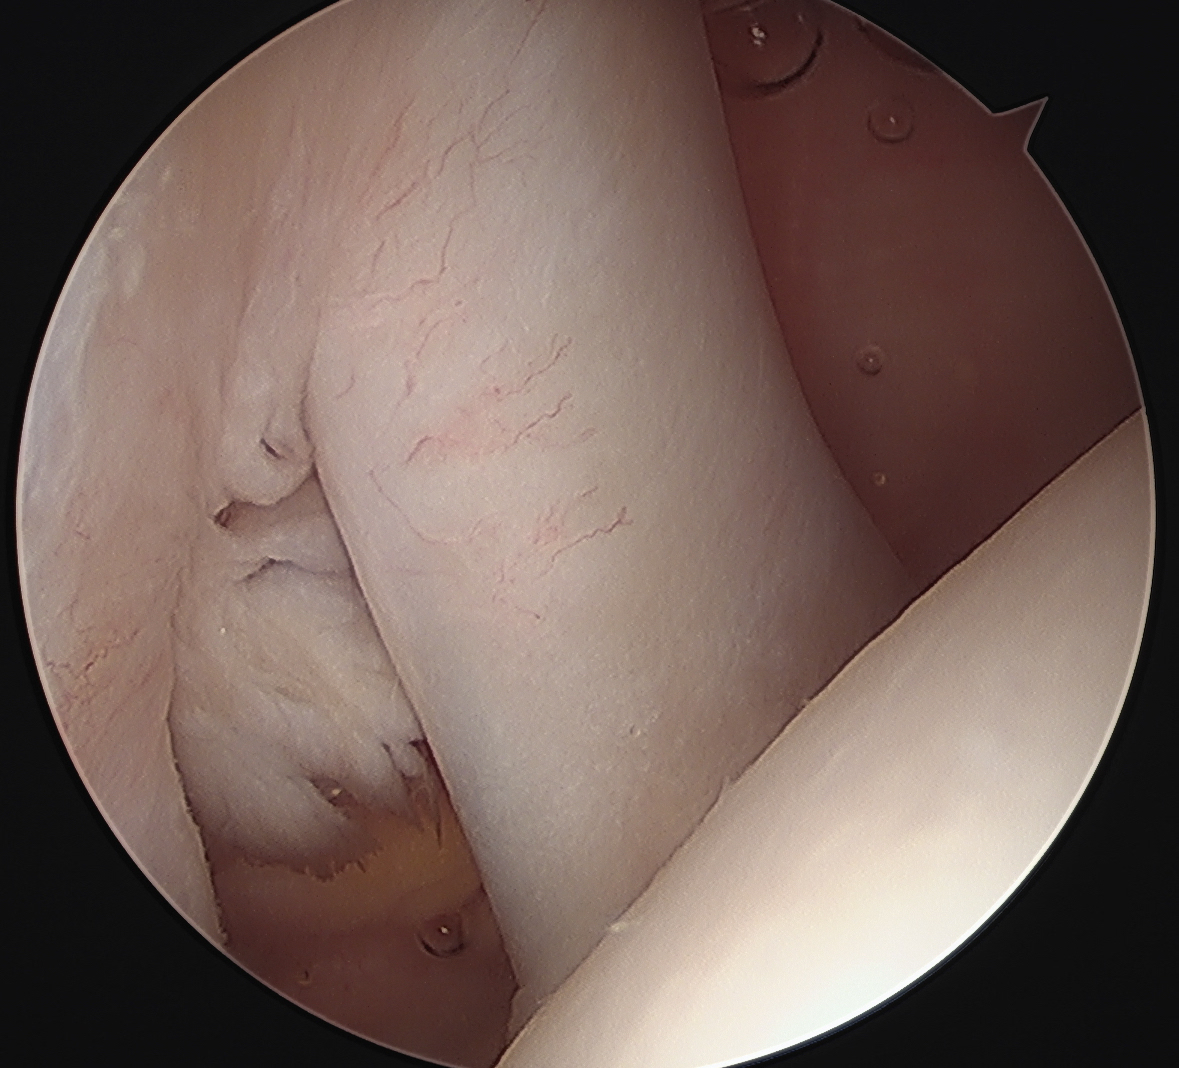

Medially dislocated biceps tendon with upper border subscapularis tear

Full thickness tear of subscapularis off insertion revealed with grasper